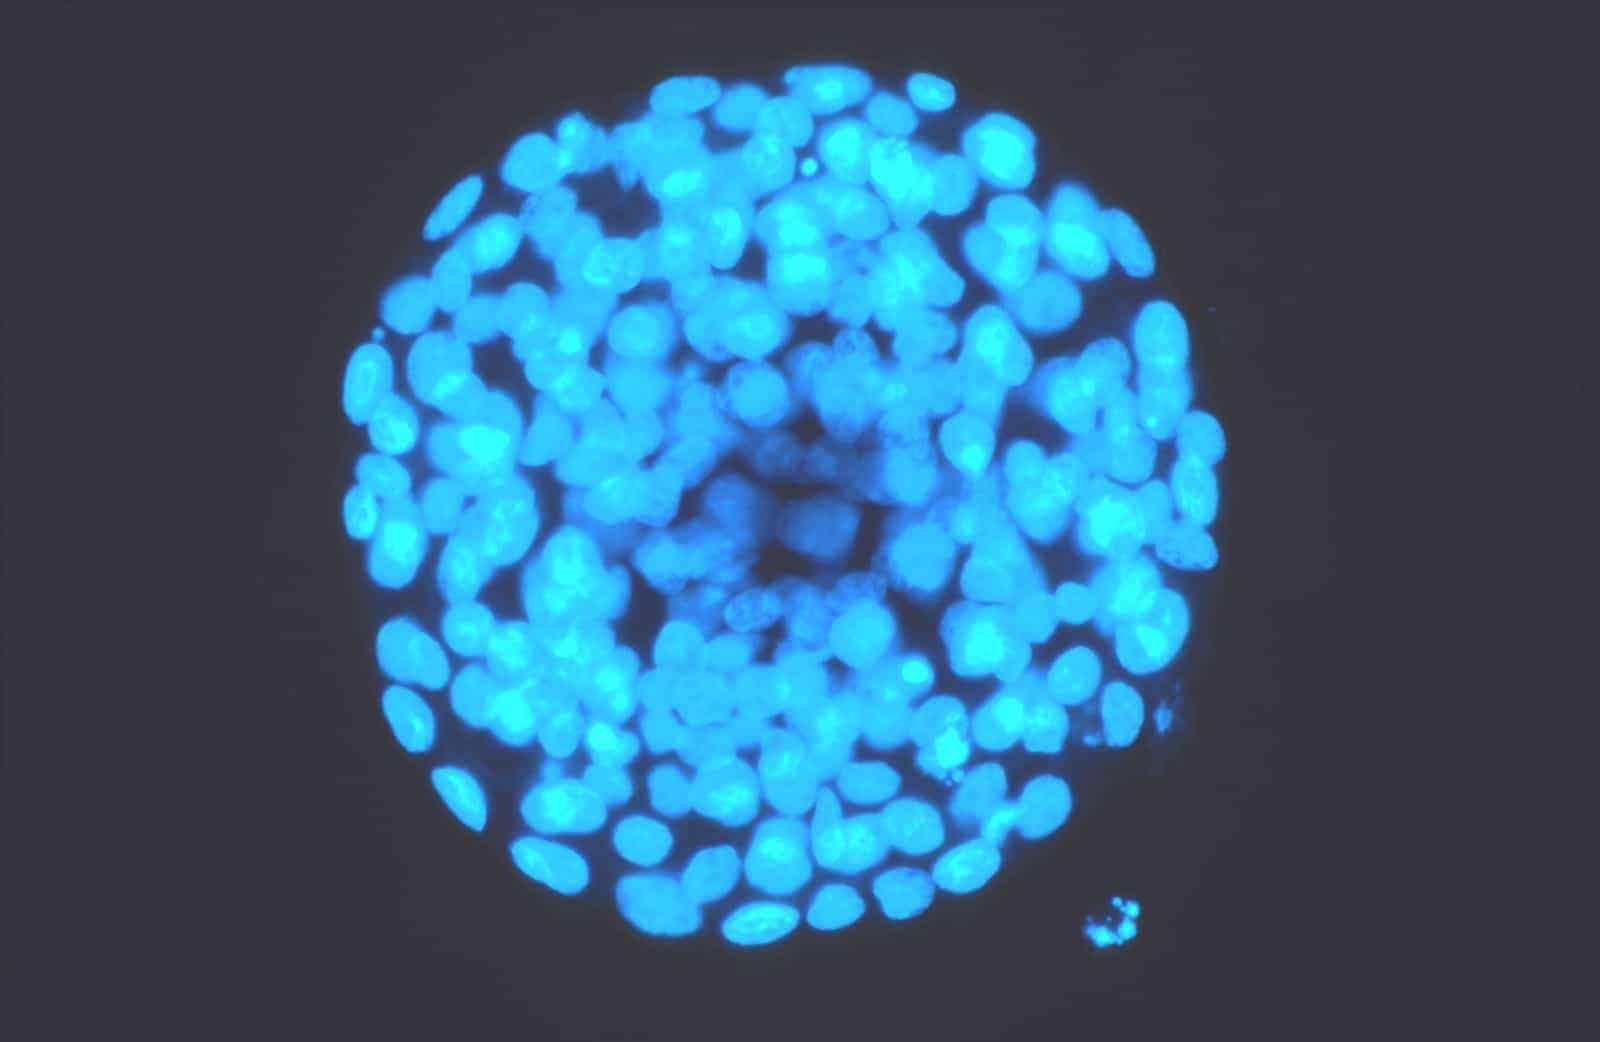

Intracytoplasmic Sperm Injection (ICSI)

With this technique, the veterinarian injects a single sperm into an egg (oocyte) in a laboratory. The fertilized oocyte can then grow in culture into an embryo, which can be transferred to a recipient mare. The procedure requires the practitioner to collect oocytes from the donor mare via transvaginal follicle aspiration (TVA), procedure that involves placing a needle through the mare’s flank. Usually, the veterinarian collects immature oocytes on a fixed schedule, recovering several oocytes at once. Mares that produce viable oocytes, yet suffer from conditions such as uterine adhesions, uterine infection, or recurrent anovulatory follicles might benefit most from ICSI, she said.